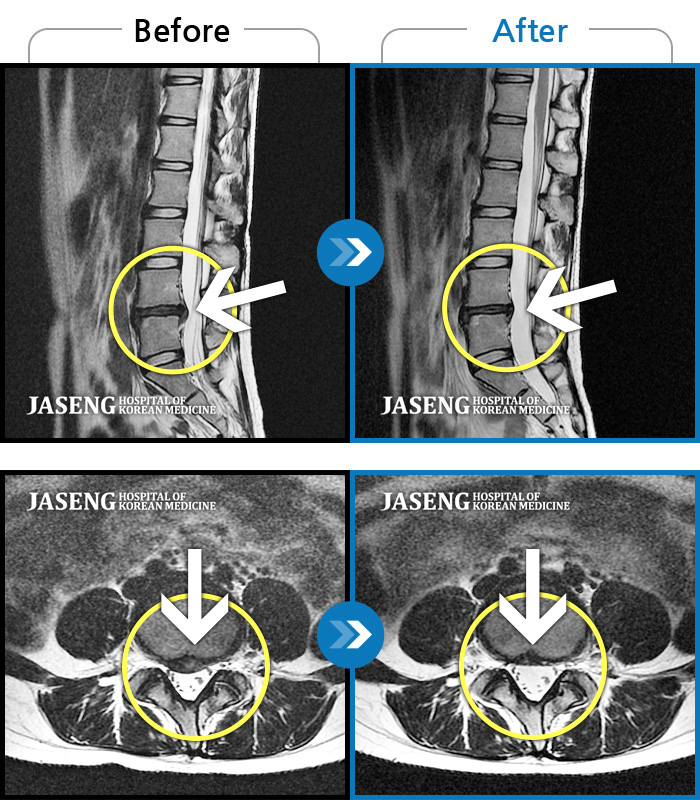

MRI로 보는 치료결과

1,169건의 MRI 전후 사진으로

터진 디스크 흡수 사례를 확인하세요.

[촬영시기:24.03.30~24.11.11]

[촬영시기:24.03.30~24.11.11]

[해운대_허리디스크] 왼쪽 허리와 종아리가 저리고 발 감각이 둔해졌어요.조회수 0 2024.11.21 -